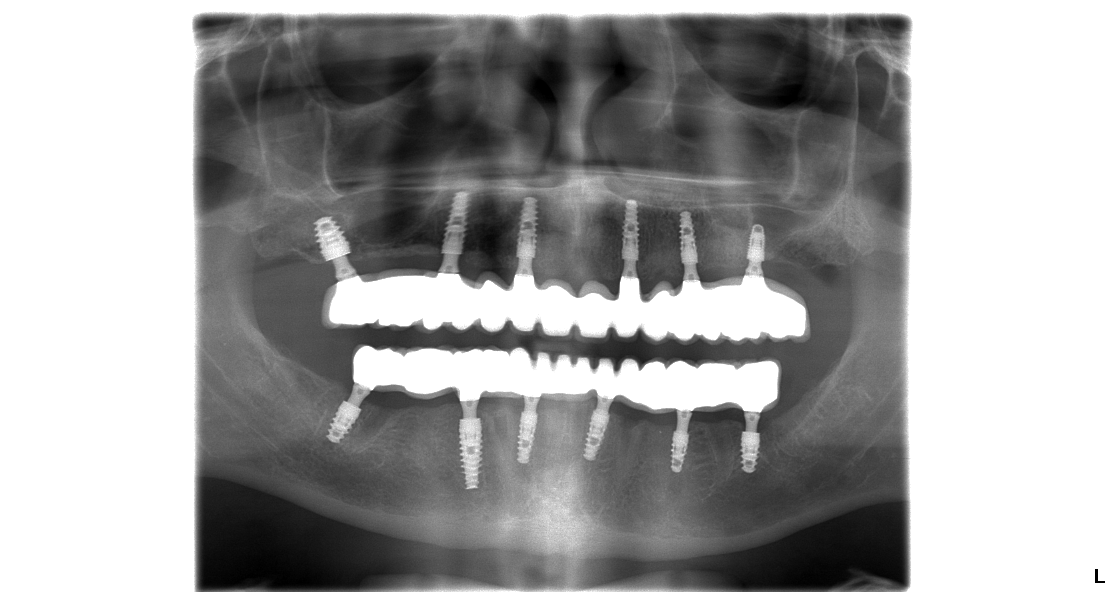

V prípade pána Tomáša bolo potrebných 6 zubných implantátov vo vrchnej a 6 zubných implantátov v spodnej čeľusti na ktoré sa nasadili 14 – členné keramické mostíky. U pni Márie bolo potrebných 7 zubných implantátov vo vrchnej čeľusti a 6 zubných implantátov v spodnej čeľusti.

Snímok pána Tomáša po dokončení ošetrenia